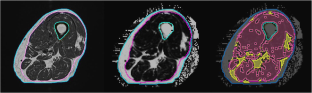

Fig. 1

Fig. 2